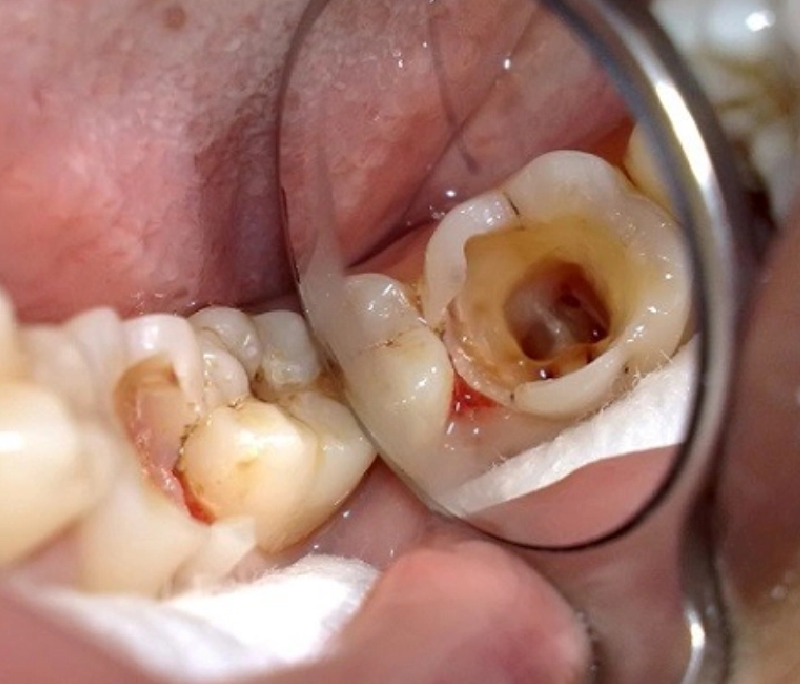

Đau răng dữ dội? Răng ê buốt kéo dài khi ăn đồ nóng lạnh? Đó có thể là những dấu hiệu cảnh báo tủy răng của ...

>> Xem ngayĐau răng dữ dội? Răng ê buốt kéo dài khi ăn đồ nóng lạnh? Đó có thể là những dấu hiệu cảnh báo tủy răng của ...